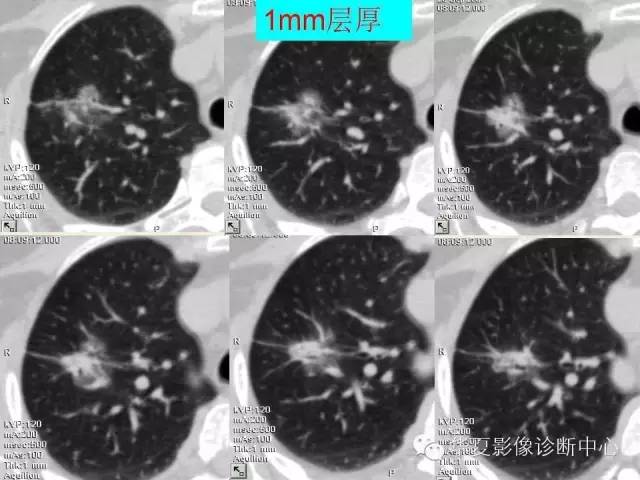

肺内磨玻璃样结节的影像诊断与处理对策